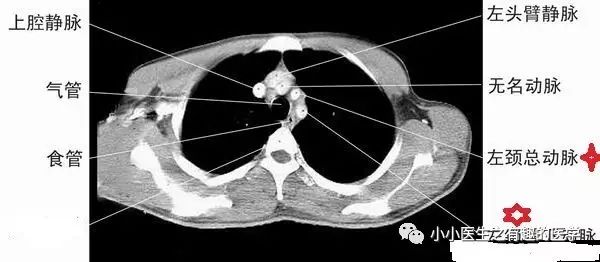

4.一定要知道主动脉弓。因为主动脉弓层面,是肺段划分的常用依据。到了主动脉弓,右肺分为前、尖、后段,左肺分为前、尖后段。这是看肺段的最基本入门知识。

另外,上腔静脉是很基本的血管,要知道。气管很重要,气管的后面,是食道。

最大的,一升一降,分别为升主动脉、降主动脉。人字形的肺动脉,剩下的为上腔静脉。

11.在胸部CT扫描中,识别众多血管是一项基础技能。对于初学者来说,重要的是要学会区分血管和可能被误认为肿瘤或淋巴结的结构。如果难以区分,进行增强CT扫描是一种有效的方法,因为血管在增强后会非常显著地显示为纯白色,而其他病变则不会如此明显。

最下边的是锁骨下动脉,锁骨下动脉上边的是颈总动脉。